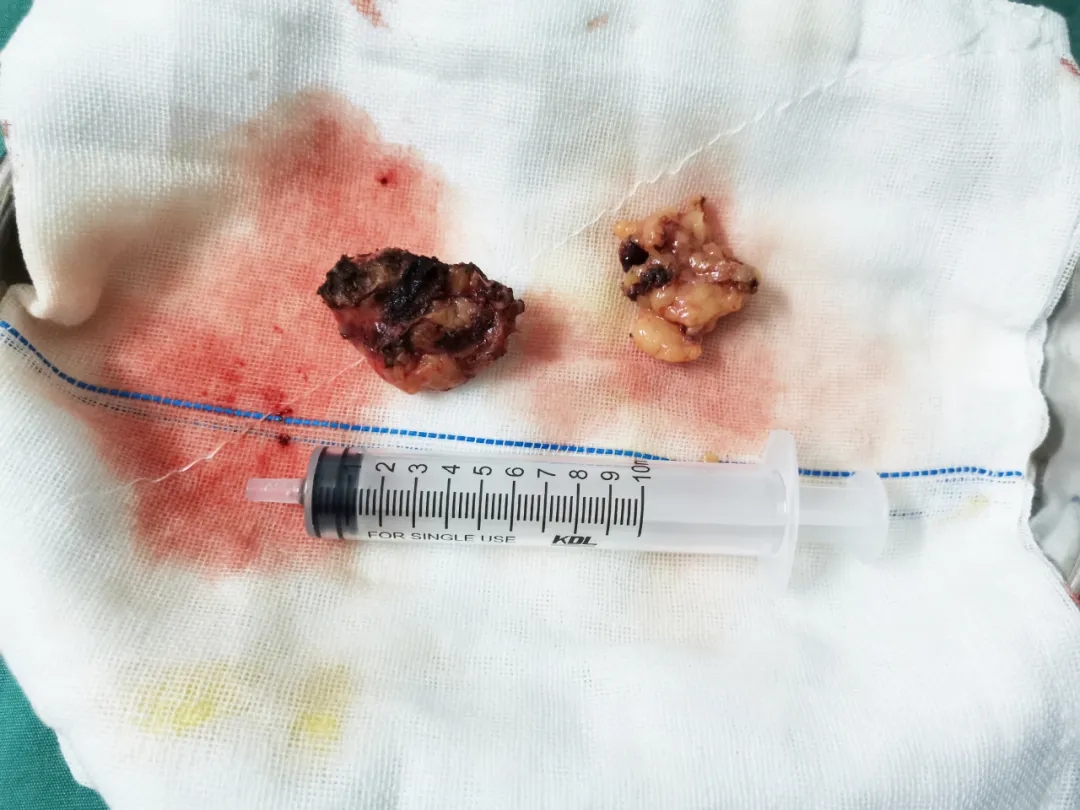

(导致黎先生腰部反复胀痛的左肾肿瘤)